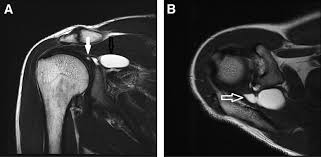

An upright mri allows patients to be scanned while standing or sitting, which can be helpful in diagnosing certain conditions. Does it seem you have no choice in where you go and what you pay for a radiology procedure? Private physios, paying for mri scans & torn shoulder problems. Estimate the cost of your mri or ct scan at american health imaging with our simple calculator. However, there are also alternatives such as ultrasound, which can also confirm rotator cuff tears.

Estimate the cost of your mri or ct scan at american health imaging with our simple calculator. $800 pesos ($43.24 usd) mri of lumbar spine without dye: Super angebote für mri procedure hier im preisvergleich. Rotator cuff tears can often be diagnosed by physical examination, but cannot be confirmed without imaging. A mri in salt lake city costs $890 on average when you take the median of the 17 medical providers who perform mri procedures in salt lake city, ut. Average prices are for mri procedures performed at honorhealth facilities around the valley, and do not include physicians' fees. When i called one facility, they told me the mri i described would cost $1,600. In different conditions, the cost for even just one mri scan can surpass $13,000. They can range from $300 to $9000. Mri spine cervical w/o cont. I went to my gp after about 6 weeks of shoulder pain who said i'd torn something in my shoulder & referred me to physio, who i saw today. Please contact your physician's office and health insurance provider directly for price information. Our experienced staff are friendly and approachable, and can answer any.

Sale de inverno shoulder com até 70% off. If a person receives an mri scan at the. But blue cross pays about half that amount: Check with your insurance provider and be tough sometimes they don't give out the info readily. However, the average shoulder mri costs around $1500. How much does a mri/ct with arthrogram cost? An upright mri allows patients to be scanned while standing or sitting, which can be helpful in diagnosing certain conditions. The national average cost for an mri at inpatient facilities is $2,250, while the same procedure at outpatient facilities averaged $650.

Estimate the cost of your mri or ct scan at american health imaging with our simple calculator. Please contact your physician's office and health insurance provider directly for price information. How much does an mri cost? If patients have not hit their deductible, that money comes straight. Surgeries / operations (head & torso) The cost of an mri will vary greatly between inpatientand outpatient facilities. How much does an mri cost? Those on high deductible health plans or without insurance can save when they buy their procedure upfront through mdsave. Although they may not say so, some physicians in health care systems or hospital groups are contracted with hospitals. If a person receives an mri scan at the. Our experienced staff are friendly and approachable, and can answer any. A shoulder mri is done to check a shoulder for arthritis, bone tumors, torn ligaments or tendons, and other similar problems. Read more about how mdsave works.